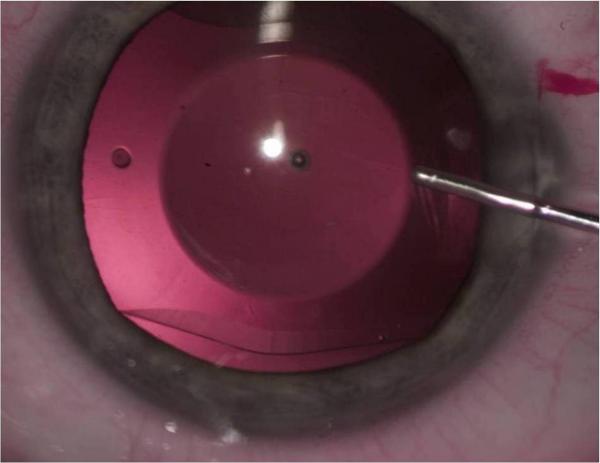

Pacjent, który 7 czerwca poddał się wszczepieniu soczewki fakijnej w klinice okulistycznej Lexummedica w Poznaniu, to 24-letni mężczyzna, cierpiący na krótkowzroczność -11 dioptrii połączoną z astygmatyzmem. Zabieg polegał na umiejscowieniu soczewki wewnątrz oka, między tęczówką, a naturalną soczewką. Pacjenta poddano znieczuleniu miejscowemu poprzez podanie kropli znieczulających do oka. Dzięki temu wszystko odbyło się dla niego bezboleśnie przy zachowaniu pełnej świadomości i kontaktu z lekarzem.

Lekarz wykonał małe nacięcie w rogówce, poprzez które wprowadził soczewkę do oka. Jest ona miękka i elastyczna, więc gdy została odpowiednio umiejscowiona, rozprostowała się sama. Teraz soczewka podtrzymywana jest przez specjalne elementy w stabilnym, bezpiecznym położeniu, dzięki czemu efekt zabiegu jest trwały i wystarczy wykonać go raz na całe życie.